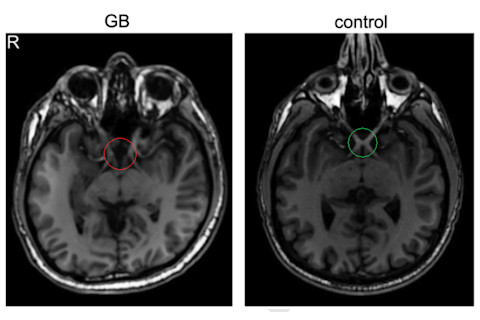

"GB" is a 28 year old man with a curious condition: his optic nerves are in the wrong place. Most people have an optic chiasm, a crossroads where half of the signals from each eye cross over the midline, in such a way that each half of the brain gets information from one side of space. GB, however, was born with achiasma - the absence of this crossover. It's an extremely rare disorder in humans, although it's more common in some breeds of animals, such as Belgian sheepdogs. Here's GB and a normal brain for comparison:

Canadian neurologists Davies-Thompson and colleagues describe GB in a new paper using functional neuroimaging to work out how his brain is organized. In the absence of a left-right crossover, all of the signals from GB's left eye end up in his left visual cortex, and vice versa. But the question was, how does the brain make sense of it? Normally, remember, each half of the cortex corresponds to half our visual field. But in GB's brain, each half has to cope with the whole visual field - twice as much space (even though it's getting no more signals than normal.) It turns out that the two halves of space overlap in GB's visual cortex, as these fMRI results show: